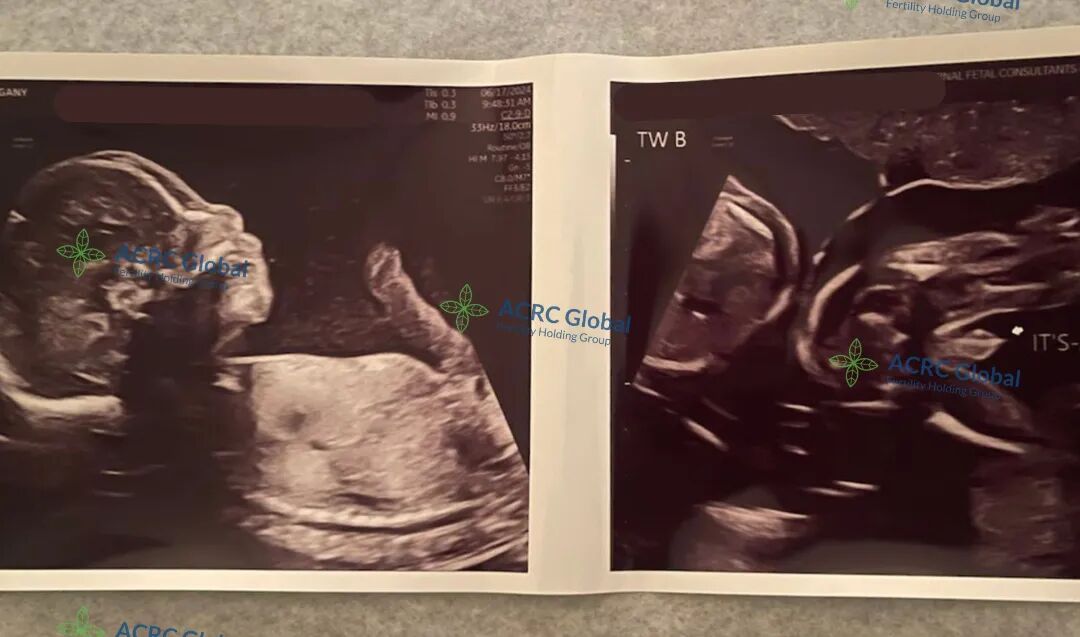

我们的单身准妈妈又收到了爱妈J最新的B超检查照片。可爱的双胞胎宝宝已经21周了,两位小家伙都非常健康,已经可以清晰地看到是两个可爱的男宝宝。准妈妈年轻时一心投入事业,无暇顾及人生大事。中年事业有成后,看到周围朋友都有了可爱的孩子,感到非常遗憾,觉得错过了最佳的生育年龄。于是她找到了我们,希望在爱妈的帮助下,也能拥有一个幸福的家庭。